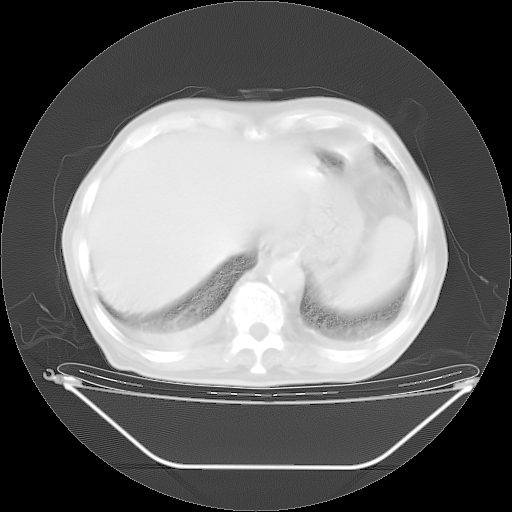

5月9日肺部CT(在4月27日齐鲁医院肺部CT描述部分肺组织磨玻璃样改变,12天后肺组织广泛磨玻璃样改变)

2009年5月9日肺部CT

大致读了系列胸部CT:纵隔窗无明显异常,肺窗:从4、27至今:主要是双肺中下野外带可见毛玻璃样改变,目前处于急性肺泡炎阶段,至于原因考虑1、结替组织或胶原血管性疾病所致?2、恶性疾病如恶组在肺部所致的表现或细支气管肺泡癌?3、药物或其它原因如肺蛋白沉着症所致肺泡炎目前不太可能?总之,明天就去请我院的呼吸科、感染科、血液科和临免专家会诊哈。